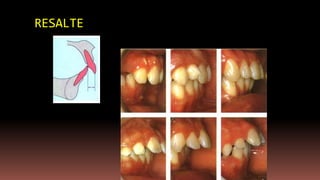

RESALTE

Resalte y sobremordida.